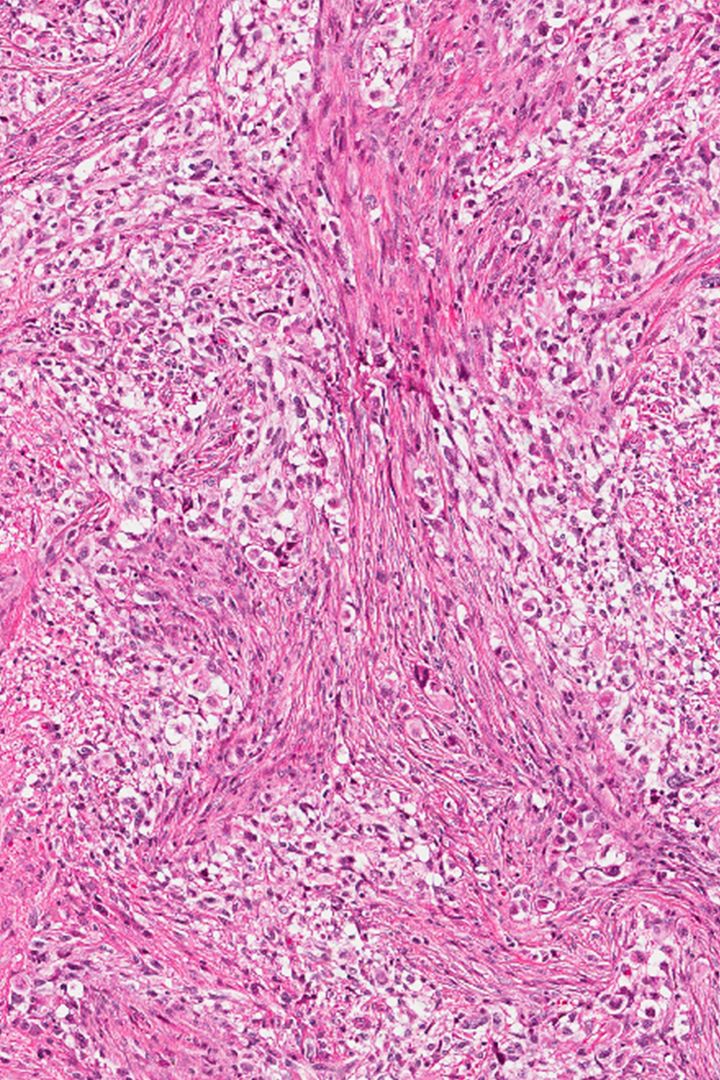

• Gliomas: The most common type of brain cancer, gliomas start in the neuroglia cells of the brain. Grade four gliomas, also known as glioblastomas, are the most aggressive type;

• Glioblastoma Multiforme (GBM), is the most common malignant brain cancer. Fewer than 5% of Australians with glioblastoma survive beyond five years.